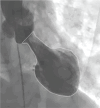

In the recent years, there has been a burgeoning interest in Takotsubo syndrome (TTS), which is renowned as a specific form of reversible myocardial dysfunction. Despite the extensive literature available on TTS, clinicians still face several practical challenges associated with the diagnosis and management of this phenomenon. This potentially results in the underdiagnosis and improper management of TTS in clinical practice. The present paper, the first part (part-1) of the consensus report, aims to cover diagnostic and therapeutic challenges associated with TTS along with certain recommendations to combat these challenges.